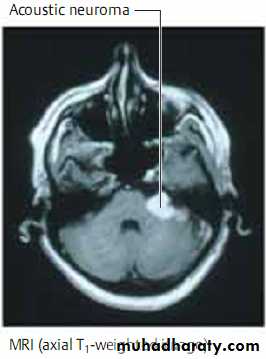

Meningeomas,acoustic neuromas &pituitary adenomas.

They are diagnosed by MRI or CT scanning which reveals marked, homogeneous contrast enhancement.